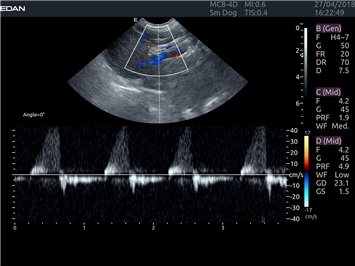

EDAN Acclarix LX4 VET

EDAN Acclarix LX4 VET представляет собой профессиональную ультразвуковую систему, специально разработанную для ветеринарных исследований. Сочетание стабильности, высокой производительности и эффективности делает эту систему идеальным выбором для современной ветеринарной практики.

Импульсно-волновой допплер:

Да

Постоянно-волновой допплер:

Триплексное сканирование: